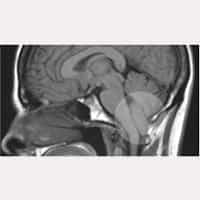

アーノルド・キアリI型症候群

脊髄空洞症

アーノルドキアリI型症候群

大後頭孔減圧術後の終糸切断手術例

特発性脊髄空洞症

シャント手術・椎弓切除術後の終糸切断手術例